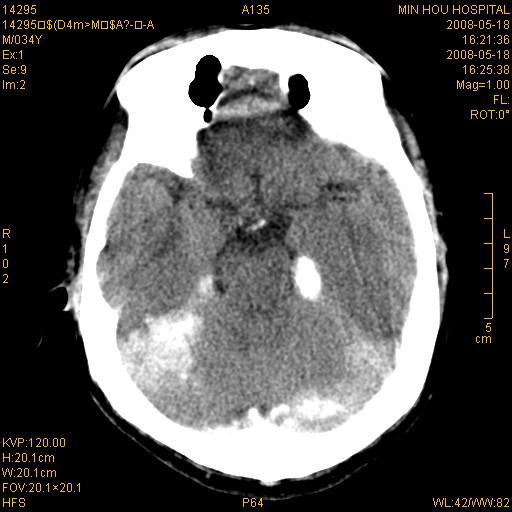

标题: CT13617:双顶叶白质水肿伴大脑镰小脑幕广泛钙化 [打印本页]

标题: CT13617:双顶叶白质水肿伴大脑镰小脑幕广泛钙化

双侧侧脑室后脚旁对称性低密度影,符合肾上腺白质营养不良(成人型)改变    小脑幕及大脑廉钙化  可考虑为生理性

支持:1、肾上腺白质营养不良.2、小脑幕、大脑镰广泛钙化。3、建议进一步检查。

硬脑膜钙化是主因,双侧顶叶白质密度减低是可能由于静脉路回流受阻所致。